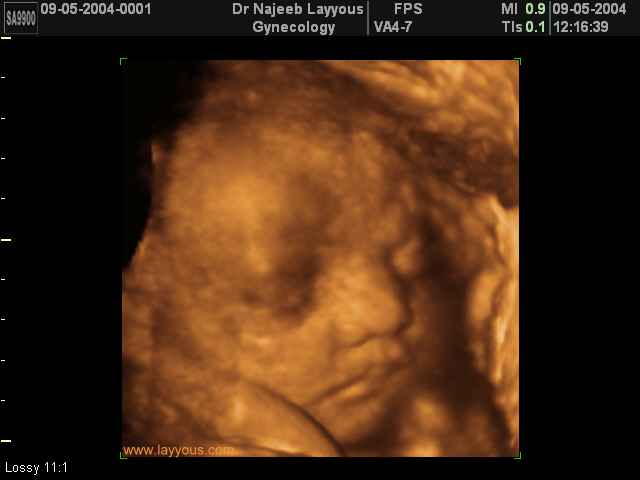

صور لوجه الجنين بجهاز الالتراساوند ثلاثي الأبعاد | الدكتور نجيب ليوس

صور لوجه الجنين بجهاز الموجات فوق صوتية ثلاثي الأبعاد